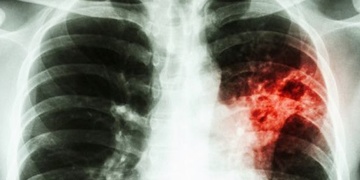

Firma sídlící na Borských polích posílá zaměstnance na rentgen plic

Agenturní dělník z Rumunska mohl ohrozit ostatní zaměstnance nákazou TBC